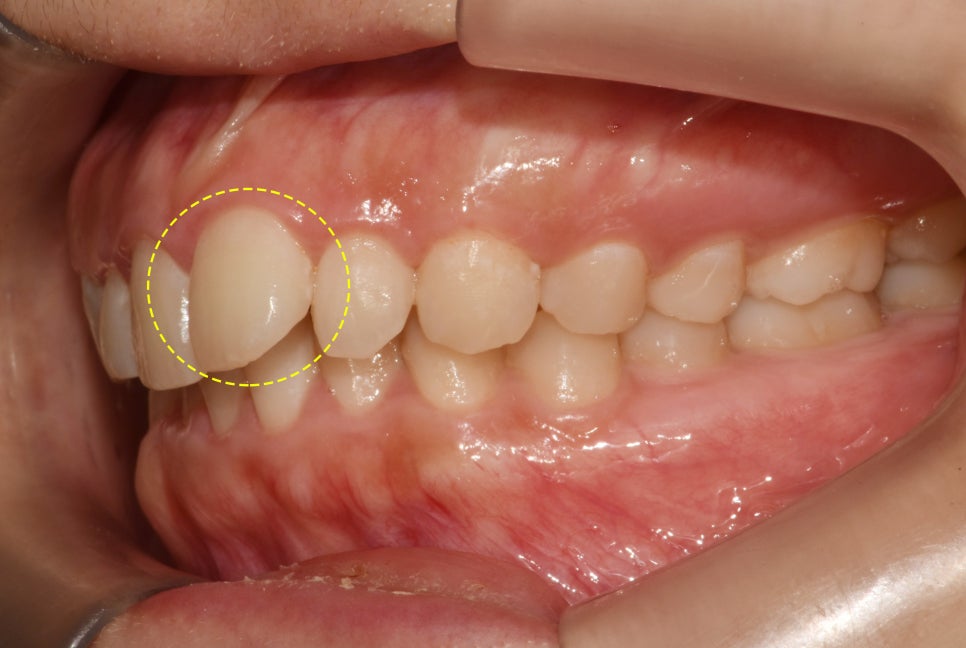

사진을 보면 왼쪽 큰 앞니인

21번 중절치가 유독 높게 올라가 있어

위치적으로 맞지 않다는 것을 볼 수 있습니다.

측면에서 보았을 때는 21번만 다른 곳들에 비해

형태가 틀어져 있어 뻐드러진 느낌으로

튀어나와 있음을 관찰할 수 있습니다.

교합면을 보면 좀 더 명확히 드러납니다.

유독 21번만 돌출되어 있는 느낌에

심미적으로도 보기에 좋지 않았습니다.

이렇게 봤을 때 외관 부분 외에

물리는 형태도 점검해 볼 필요가 있습니다.